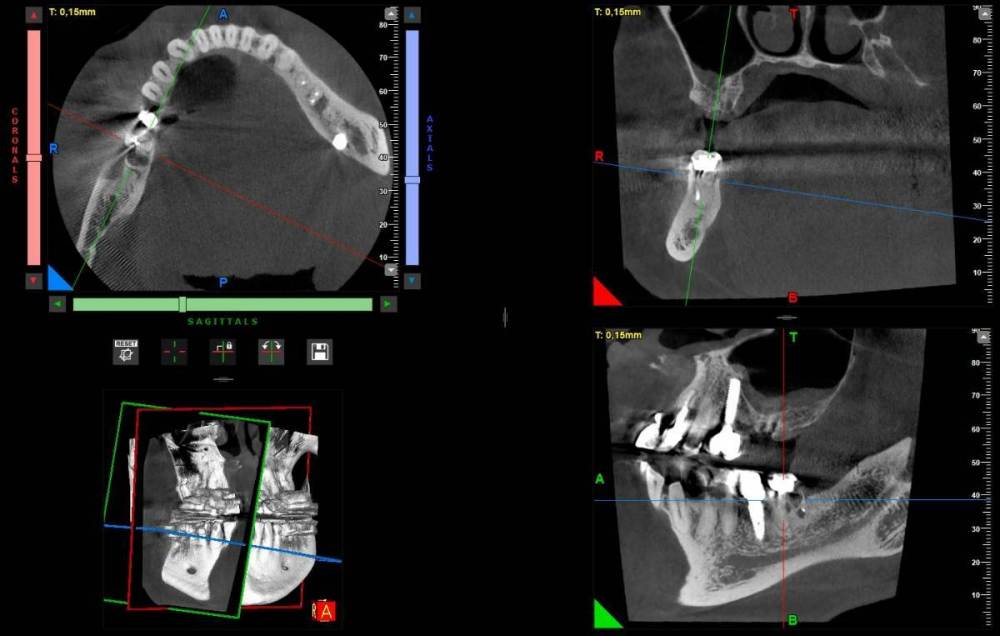

3. По поводу результатов проведенной имплантации 7 лет назад.  Один хирург  который смотрел мой снимок недавно выразил мнение, что импланты на верних челюстях выбраны избыточной длины и можно было просто поставить импланты большего диаметра и короче. Он увидел признаки резорбции кости.  Хотел бы услышать ваше мнение об этом и на сколько прав он в своих суждениях. Сколько лет еще могут простоять установленные импланты ? Про врачебную этику и пациентов знаю, но мы не раскрываем имя доктора, а если не хотите писать открыто можно написать мне в личку.  Для меня это очень важно. К доктору я естественно без претензий, но на выбор для новых операции безусловно повлияет.  Спасибо большое за то, что вы  прочитали и ваше мнение!

Компьютерная томография: https://cloud.mail.ru/public/nnZJ/N2pid2KKF

1. Зуб 16 удалять вне всяких сомнений. Закрытый или открытый синус-лифтинг? Решение будет принимать хирург, который будет вас оперировать.

3. Высказывания консультанта остаются на его совести. На мой взгляд, особо придраться не к чему. Хотя, "докопаться" и до столба можно.